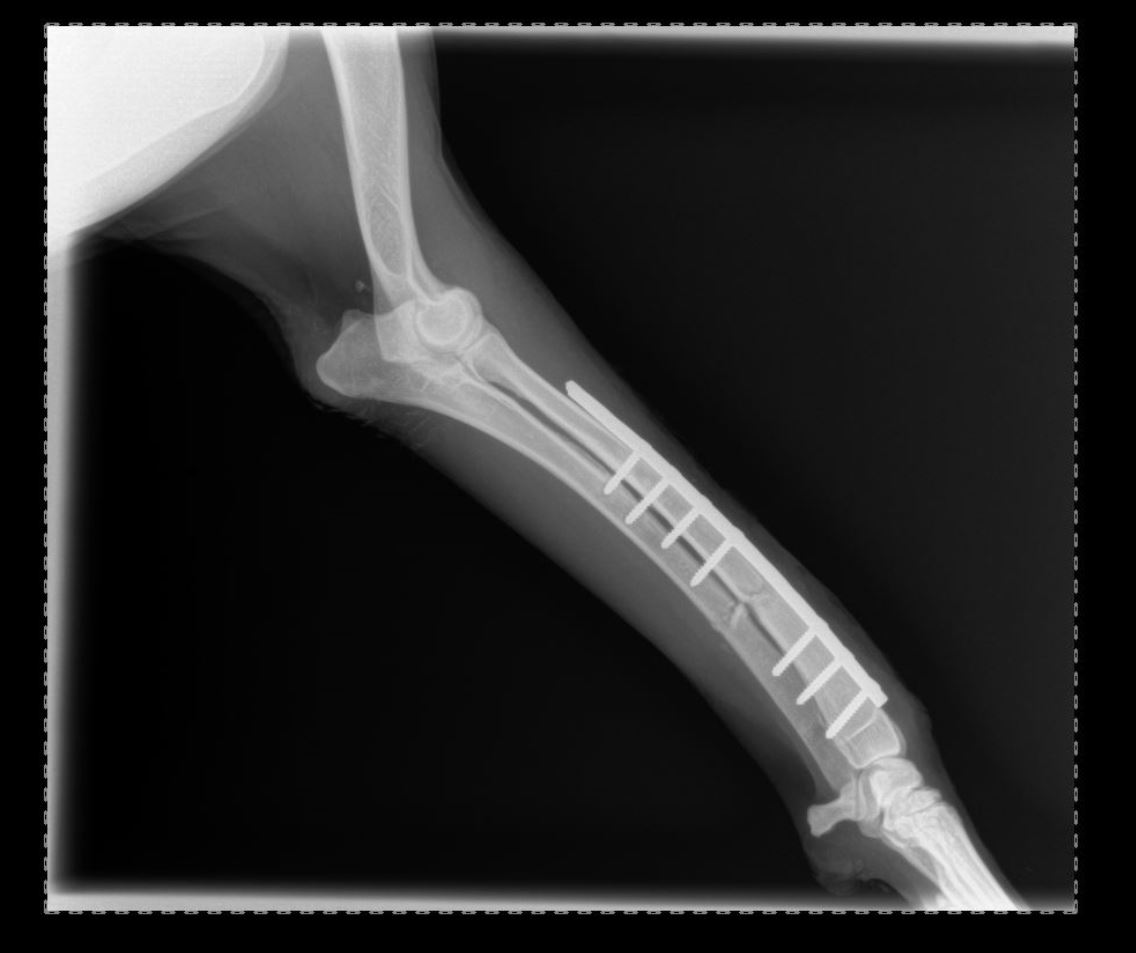

Pose implant plaque DCP

-réduction des fractures (pose divers implants plaques broches etc),

Chirurgies orthopediques: